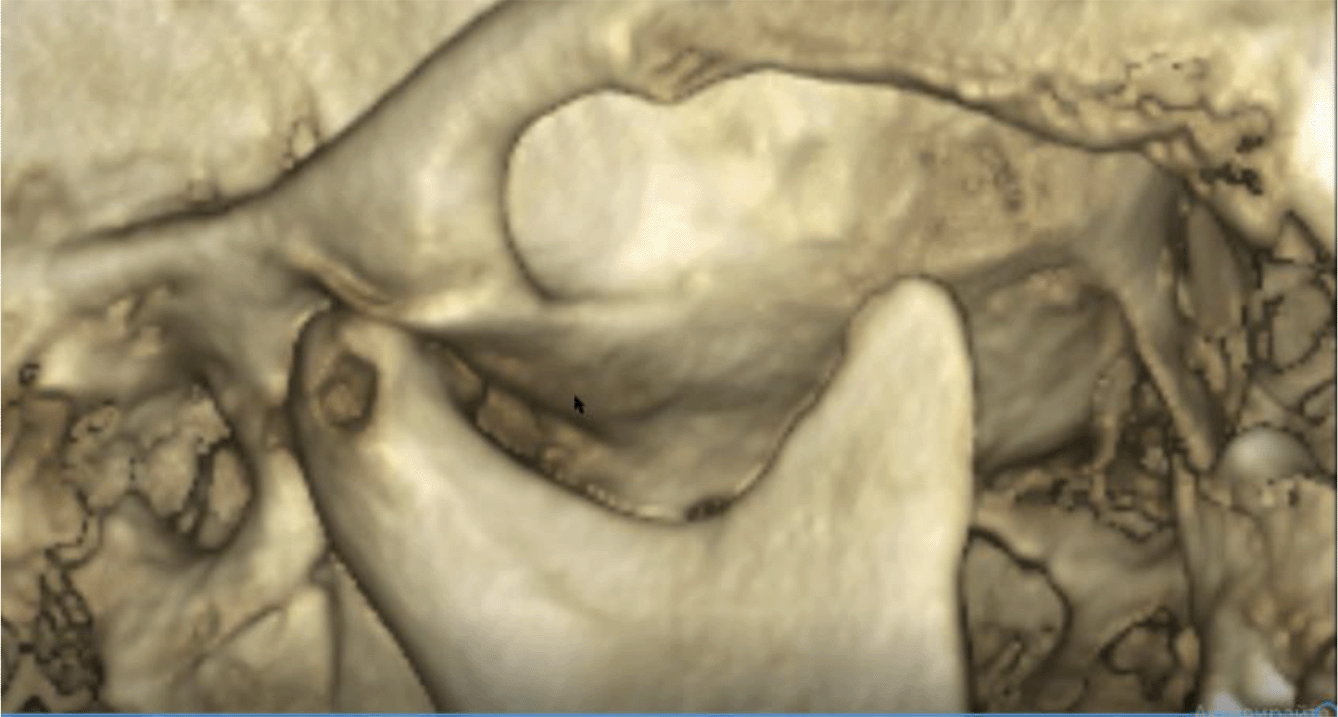

A cone beam CT (CBCT) scan showed an intra-articular problem in the right TMJ. The processus condylaris mandibulae had a preserved convex shape, but its lateral side was in contact with the eminentia articularis. The joint gap between these structures was asymmetric - wider medially and narrower laterally. In the medio-distal direction, the articular condyle was positioned more distally than the normal physiological position. The presence of osteophyte laterally was also established. The left TMJ did not show deviations from the norm (Figures 5 and 6).

26dd931c-41d3-478d-bec1-8cb211d0a4b8_figure5.gif

Figure 5. CBCT visualization – right and left TMJ.

26dd931c-41d3-478d-bec1-8cb211d0a4b8_figure6.gif

Figure 6. Right TMJ condition with osteophyte.